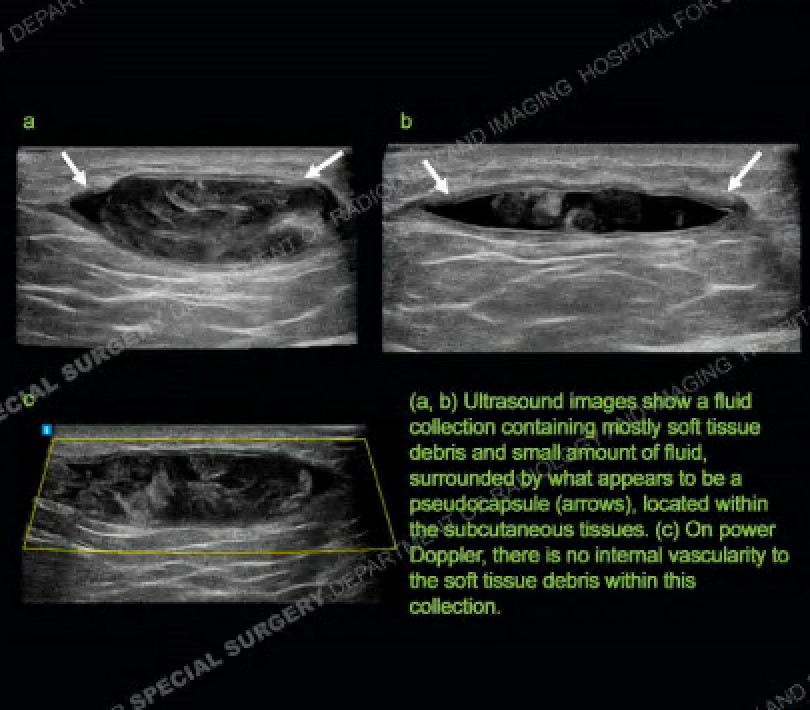

Celebrate Medical Ultrasound Awareness Month by diagnosing recent case. 66-year-old male with lateral thigh pain. Patient reports history of previous trauma to this area. Identify the diagnosis from the teaching files of the #1 hospital in orthopedics: https://t.co/aCnPK80pq2